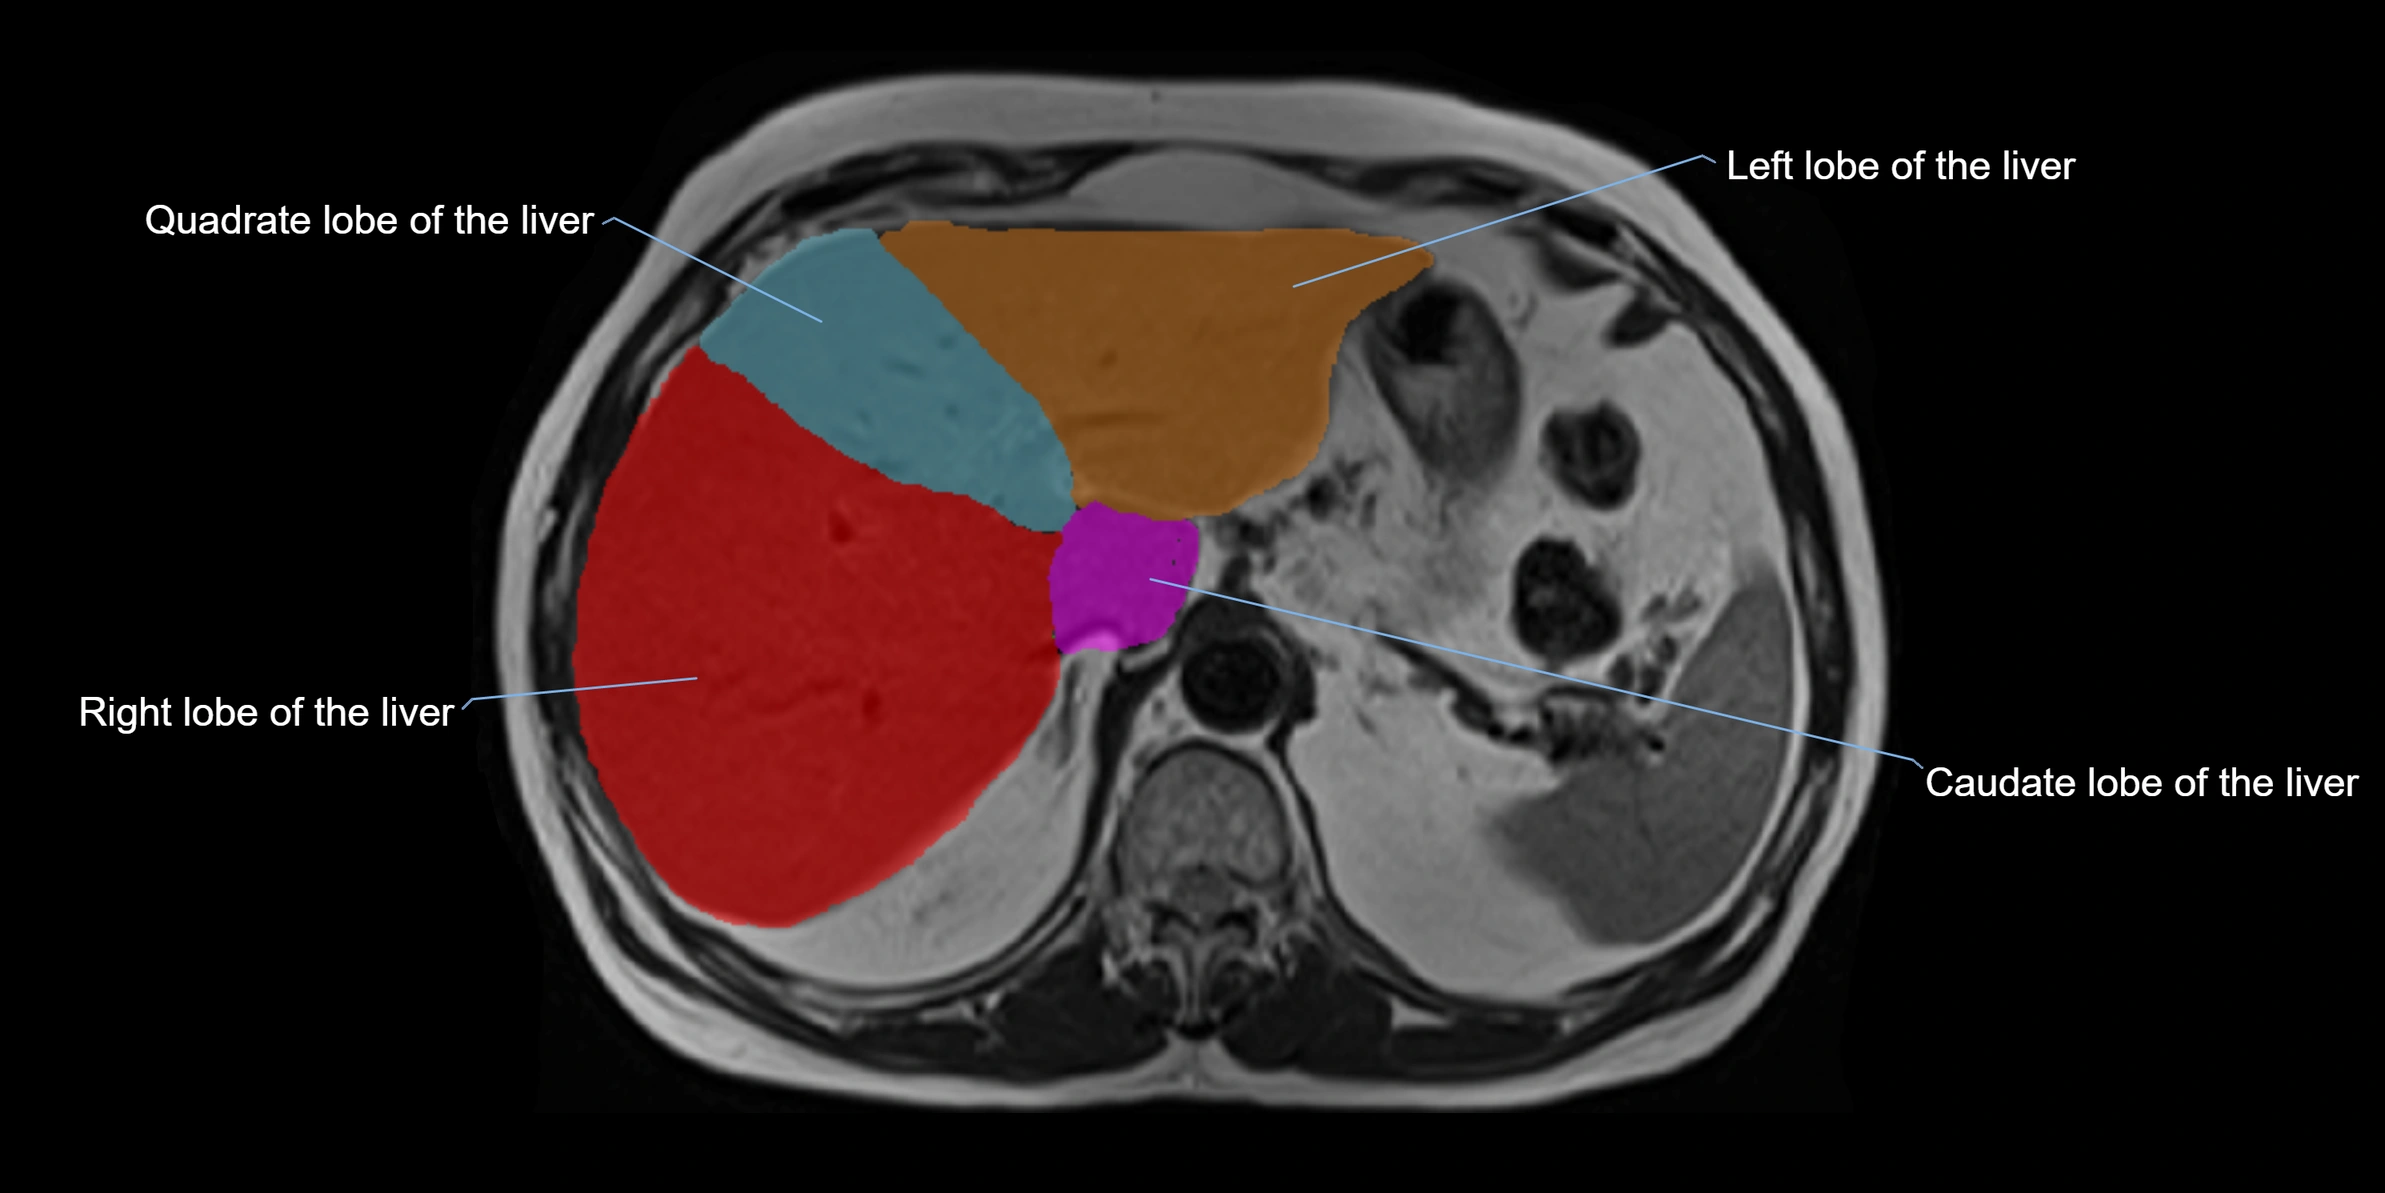

The caudate lobe of the liver is a distinct anatomical subdivision of the liver, designated as segment I in Couinaud’s classification. It lies on the posterior surface of the liver, between the fissure for the ligamentum venosum (left boundary) and the groove for the inferior vena cava (IVC) (right boundary). Superiorly, it is related to the posterior liver surface, and inferiorly it is separated from the left lobe by the porta hepatis.

The caudate lobe is unique because it receives dual portal venous and arterial inflow from both the right and left portal veins and hepatic arteries. It also has independent venous drainage directly into the IVC via multiple small hepatic veins, unlike other lobes that drain through the three main hepatic veins.

This anatomical autonomy makes the caudate lobe especially significant in liver surgery, transplantation, and hepatic venous outflow obstruction syndromes (e.g., Budd–Chiari syndrome). Enlargement of the caudate lobe is a characteristic imaging feature in chronic liver disease and cirrhosis.